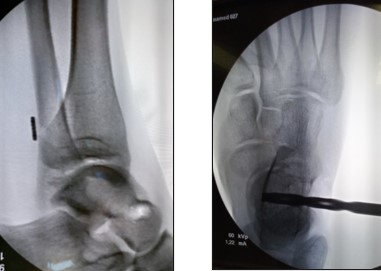

Второй этап – восстановления передней таранно-малоберцовой связки.

Выполняется линейный кожный разрез 4,5 см, отступая от переднего края латеральной лодыжки в направлении головки таранной кости (рис.E ) После рассечения подлежащих мягких тканей выполняется ревизия голеностопного сустава. При помощи специальный направителей сформированы малоберцовый туннель (рис. F) и туннель в таранной кости (рис.G ), диаметр которых соответствует диаметру трансплантата. Выполнена реконструкция передней таранно-малоберцовой связки правого голеностопного сустава: фиксация в малоберцовой кости пуговицей, фиксация в таранной кости интерферентным винтовым фиксатором 7-30мм. (рис.I ). Гемостаз по ходу операции. Рана обработана растворами ансисептиков. Послойное ушивание раны. Швы на кожу (рис. K) Асептическая повязка. Эластическая компрессия конечности. Ортезная иммобилизация.

Рис. 7.4 E,F,G,H,I,K— восстановлениe передней таранно-малоберцовой связки аутотрансплантатом из сухожилия полусухожильной мышцы

E- линейный кожный разрез; F- формированы туннеля в малоберцовой кости; G- формированы туннеля в таранной кости; H- проведение аутотрансплантата из сухожилия полусухожильной мышцы в малоберцовой кости; I- проведение аутотрансплантата из сухожилия полусухожильной мышцы в таранной кости и его фиксация; K-вид послеоперационной раны